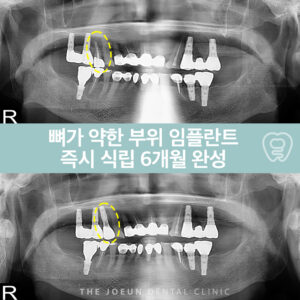

잇몸뼈가 가장 약했던 오른쪽 위 어금니 부위는 다른 부위에 모든 보철물을 합착한 뒤 식립을 진행하였는데요.

임플란트 수술의 핵심은 잇몸뼈입니다. 치아를 지탱하는 치조골은 임플란트를 식립하는데 가장 중요한 기반이 되며 양질의 잇몸뼈가 확보되지 않으면 단 한개의 인공치근조차 안정적으로 고정하기 어려우며 치아를 오랫동안 상실한 상태로 두면 잇몸뼈가 점점 흡수되어 얇아져 이 경우에는 뼈이식을 통해 기반을 보강하는 과정이 필요합니다. 이러한 사전 준비가 되어야 식립 후에도 안정성과 저작력을 확보할 수 있습니다.